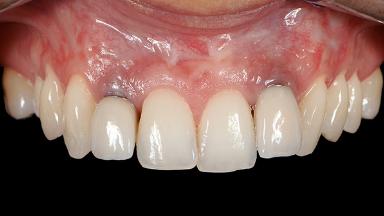

Periodontal Plastic Surgery and Prosthetic Procedures to Treat Peri-Implant Soft-Tissue Dehiscences

A 30-year-old woman was referred by her general dentist for evaluation of an esthetic complication related to previous implant treatment for congenitally missing maxillary lateral incisors. The patient’s chief complaint was the inadequate esthetic appearance of her smile. The case demonstrates the use of a combined approach to achieve optimal results. Two different flap designs - a tunnel technique and a coronally advanced flap - are employed based on the surgical objectives for the affected site.

Soft Tissue Grafting Yes